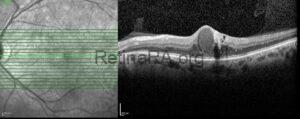

Peripapillary Hyperreflective Ovoid Mass-Like Structures (PHOMS)

An 8-year-old male patient was referred to our clinic with a suspicion of papilledema. The [...]